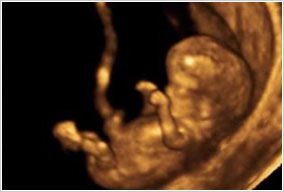

If You Are Pregnant

If you are near your due date please call when your contractions are regular and getting progressively more painful, if you’re leaking fluid or bleeding, If you have a fever or severe nausea or vomiting and/or headache that didn’t respond to Tylenol. Please call if you’re experiencing significant decrease in fetal movements.